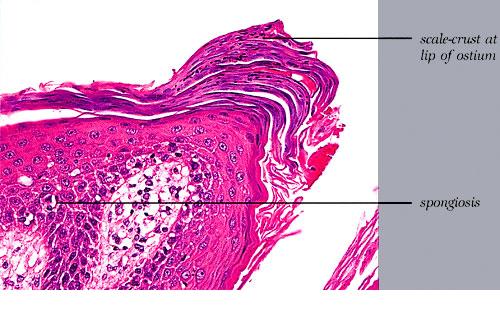

Histopathology. The histopathologic features are a combination of those observed in psoriasis and spongiotic dermatitis. Mild cases may exhibit only slight subacute spongiotic dermatitis. The stratum corneum contains focal parakeratosis, with a predilection for the follicular ostia, a finding known as shoulder parakeratosis . Occasional pyknotic neutrophils are present within parakeratotic foci {neutrophilic parakeratosis}, sometimes with fluid {neutrophilic crust}. There is moderate acanthosis with regular elongation of the rete ridges, mild spongiosis, and focal exocytosis of lymphocytes. The dermis contains a sparse mononuclear cell infiltrate. In HIV-infected patients, the epidermis contains apoptotic keratinocytes, and the dermal infiltrate usually contains plasma cells. |